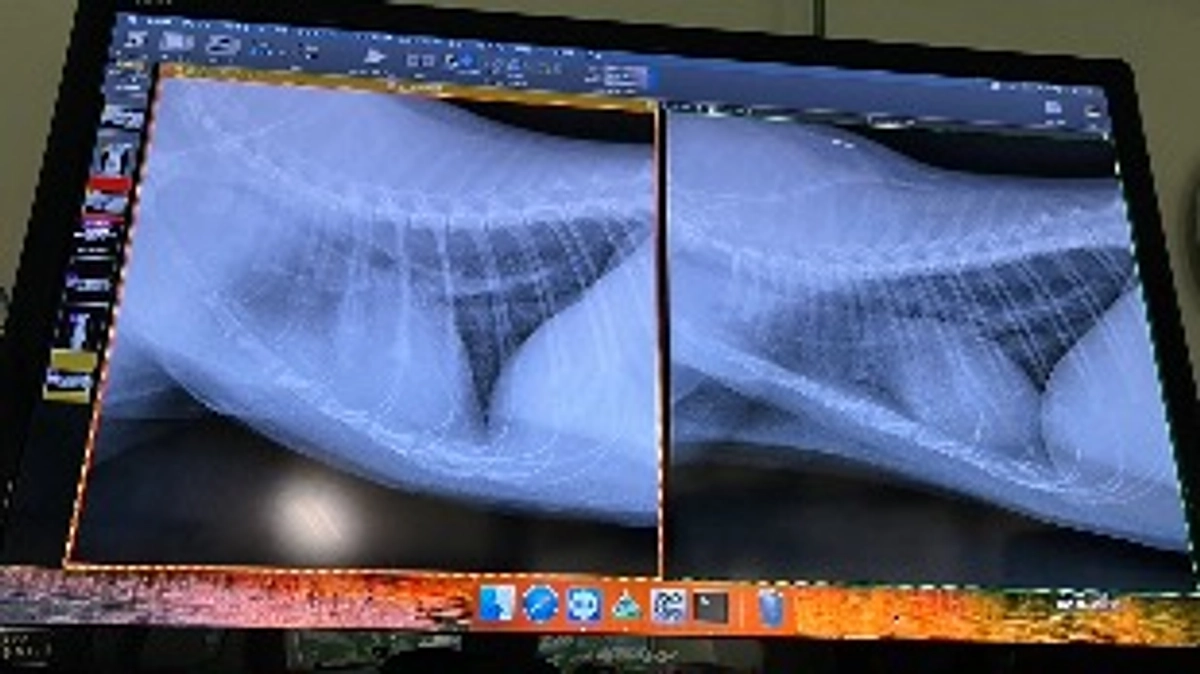

血液検査の数値はよかったのですが、レントゲンでは心臓付近に曇りが、、とのことでした。

FIPになり胸水が貯まっていたのは、無くなっていました。

しかし、前回のレントゲンより、心臓のくもりは気になるものなようで、様子を見ることになりました。

恐らく、コアがすぐに息切れ(パンティング)するのは、これが原因では無いか、とのことでした。